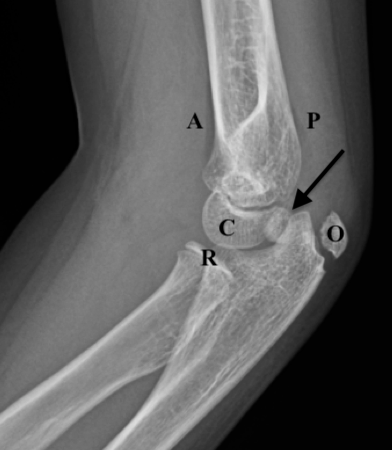

Figure 9B: Lateral view with markings. Ossification centers of capitellum (C), radial head (R), and olecranon (O), are seen. The internal (medial) epicondyle is identified by the arrow, avulsed into the joint. There is also, again slightly rotated, a small anterior fat pad seen (A) (not a “sail,” so this is normal) and very small posterior fat pad (P) (always abnormal).